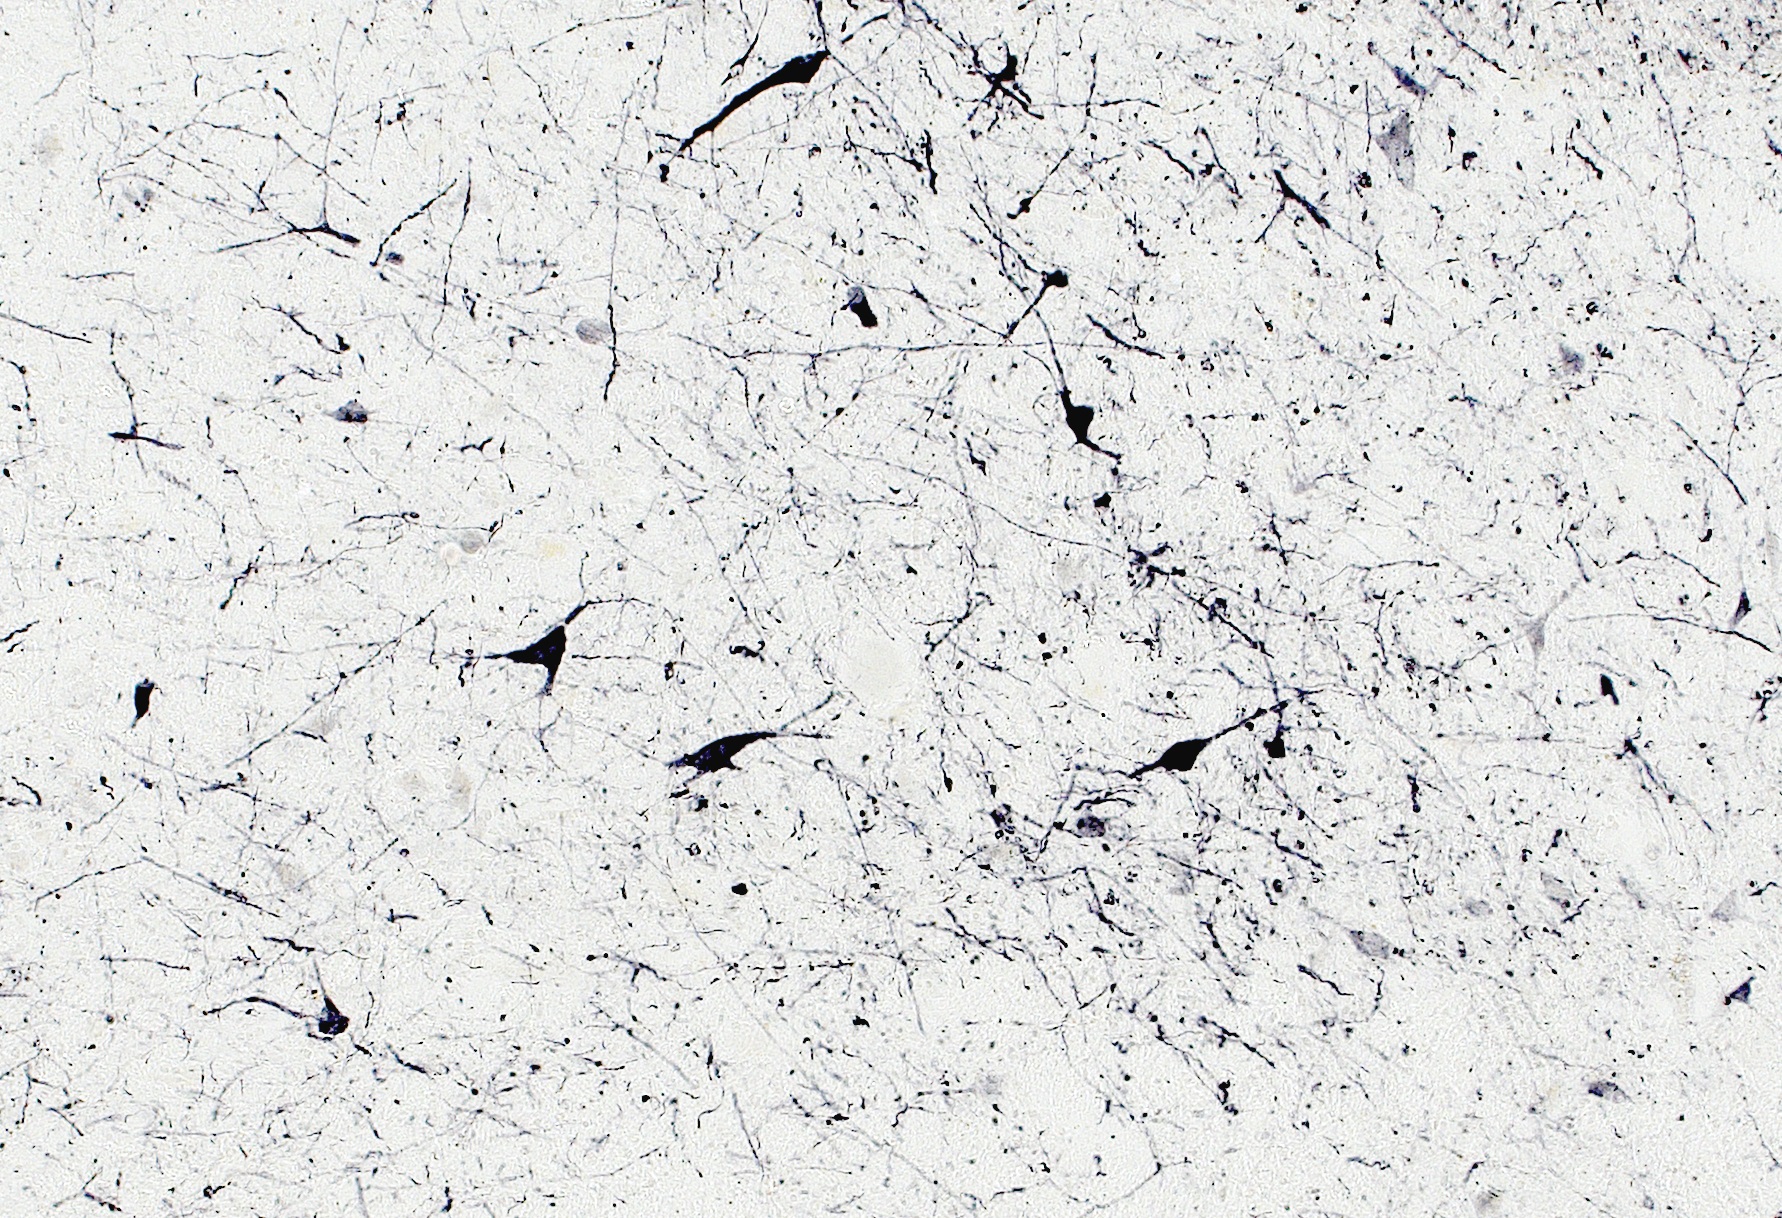

IHC Results Cryosections of Human Hypothalamus. Recommended dilution range: 1:10000 - 1:40000. | |